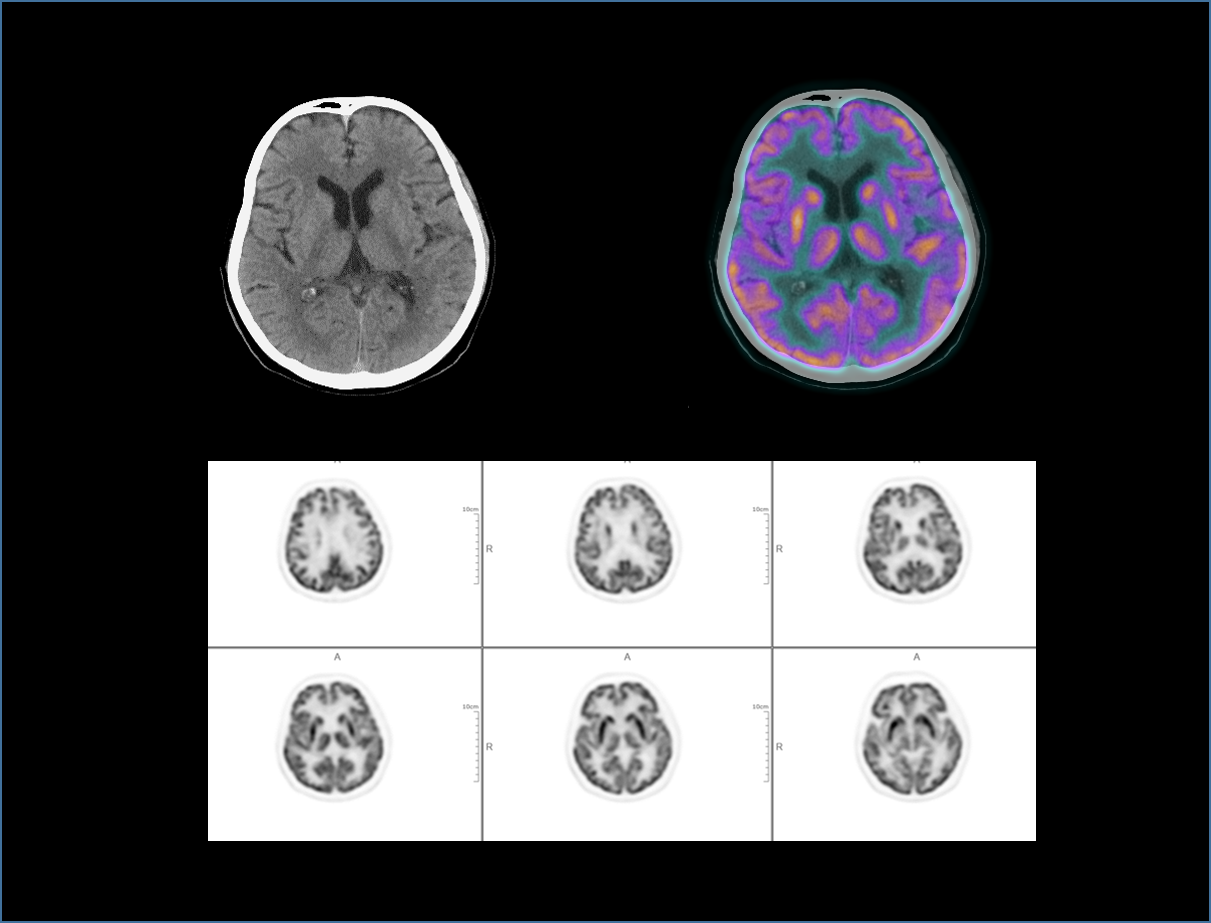

160-warstwowy skaner TK o wysokich parametrach

Obrazowanie TK o wysokiej rozdzielczości czasowej.

Niższa dawka promieniowania i wyższy kontrast obrazu.

Wysoki stosunek sygnału do szumu i jakość obrazu.

Wysoka rozdzielczość przestrzenna umożliwiająca wizualizację drobnych szczegółów anatomicznych.